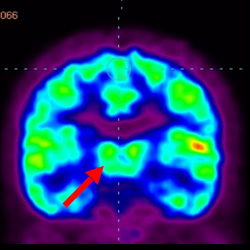

細(xì)胞治療前PET CT掃描顯示神經(jīng)組織中的藍(lán)/黑色區(qū)域,表明腦癱引起的大腦損傷。

腦癱細(xì)胞療法, 腦癱治療